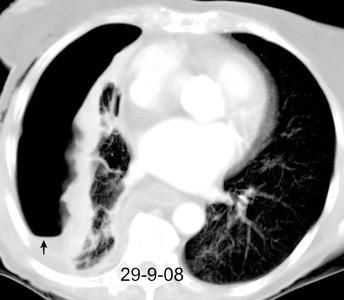

Nefrectomia derecha en 1996 por adenocarcinoma renal. Reseccion de metastasis pulmonar en LSI de carcinoma renal. Sospecha de nueva metástasis.